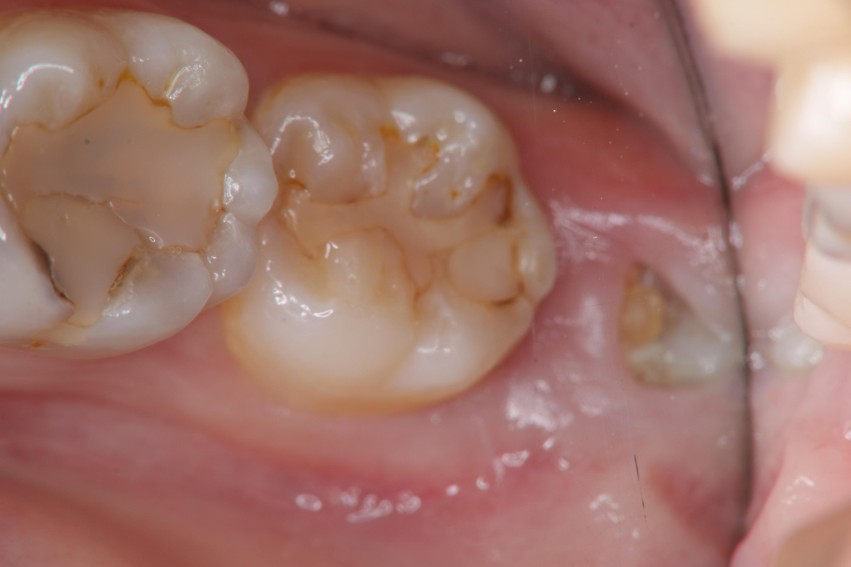

治療前

治療前,阻生齒牙齦經常腫脹